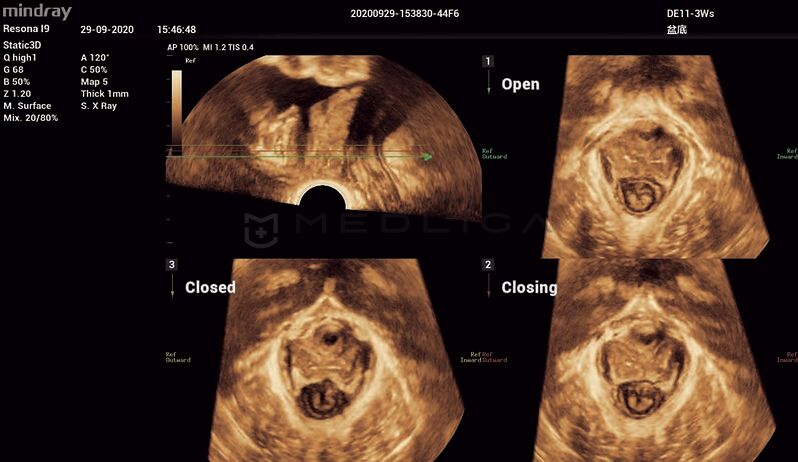

Программное обеспечение для автоматических измерений параметров и оценки функции мышц тазового дна.

Smart Pelvic - новое решение, позволяющее значительно упростить диагностическую процедуру и свести к минимуму время исследования функций мышц тазового дна. Благодаря чрезвычайно простому пользовательскому интерфейсу, программа генерирует стандартную систему координат и автоматически просчитывает все связанные измерения в течение нескольких секунд.